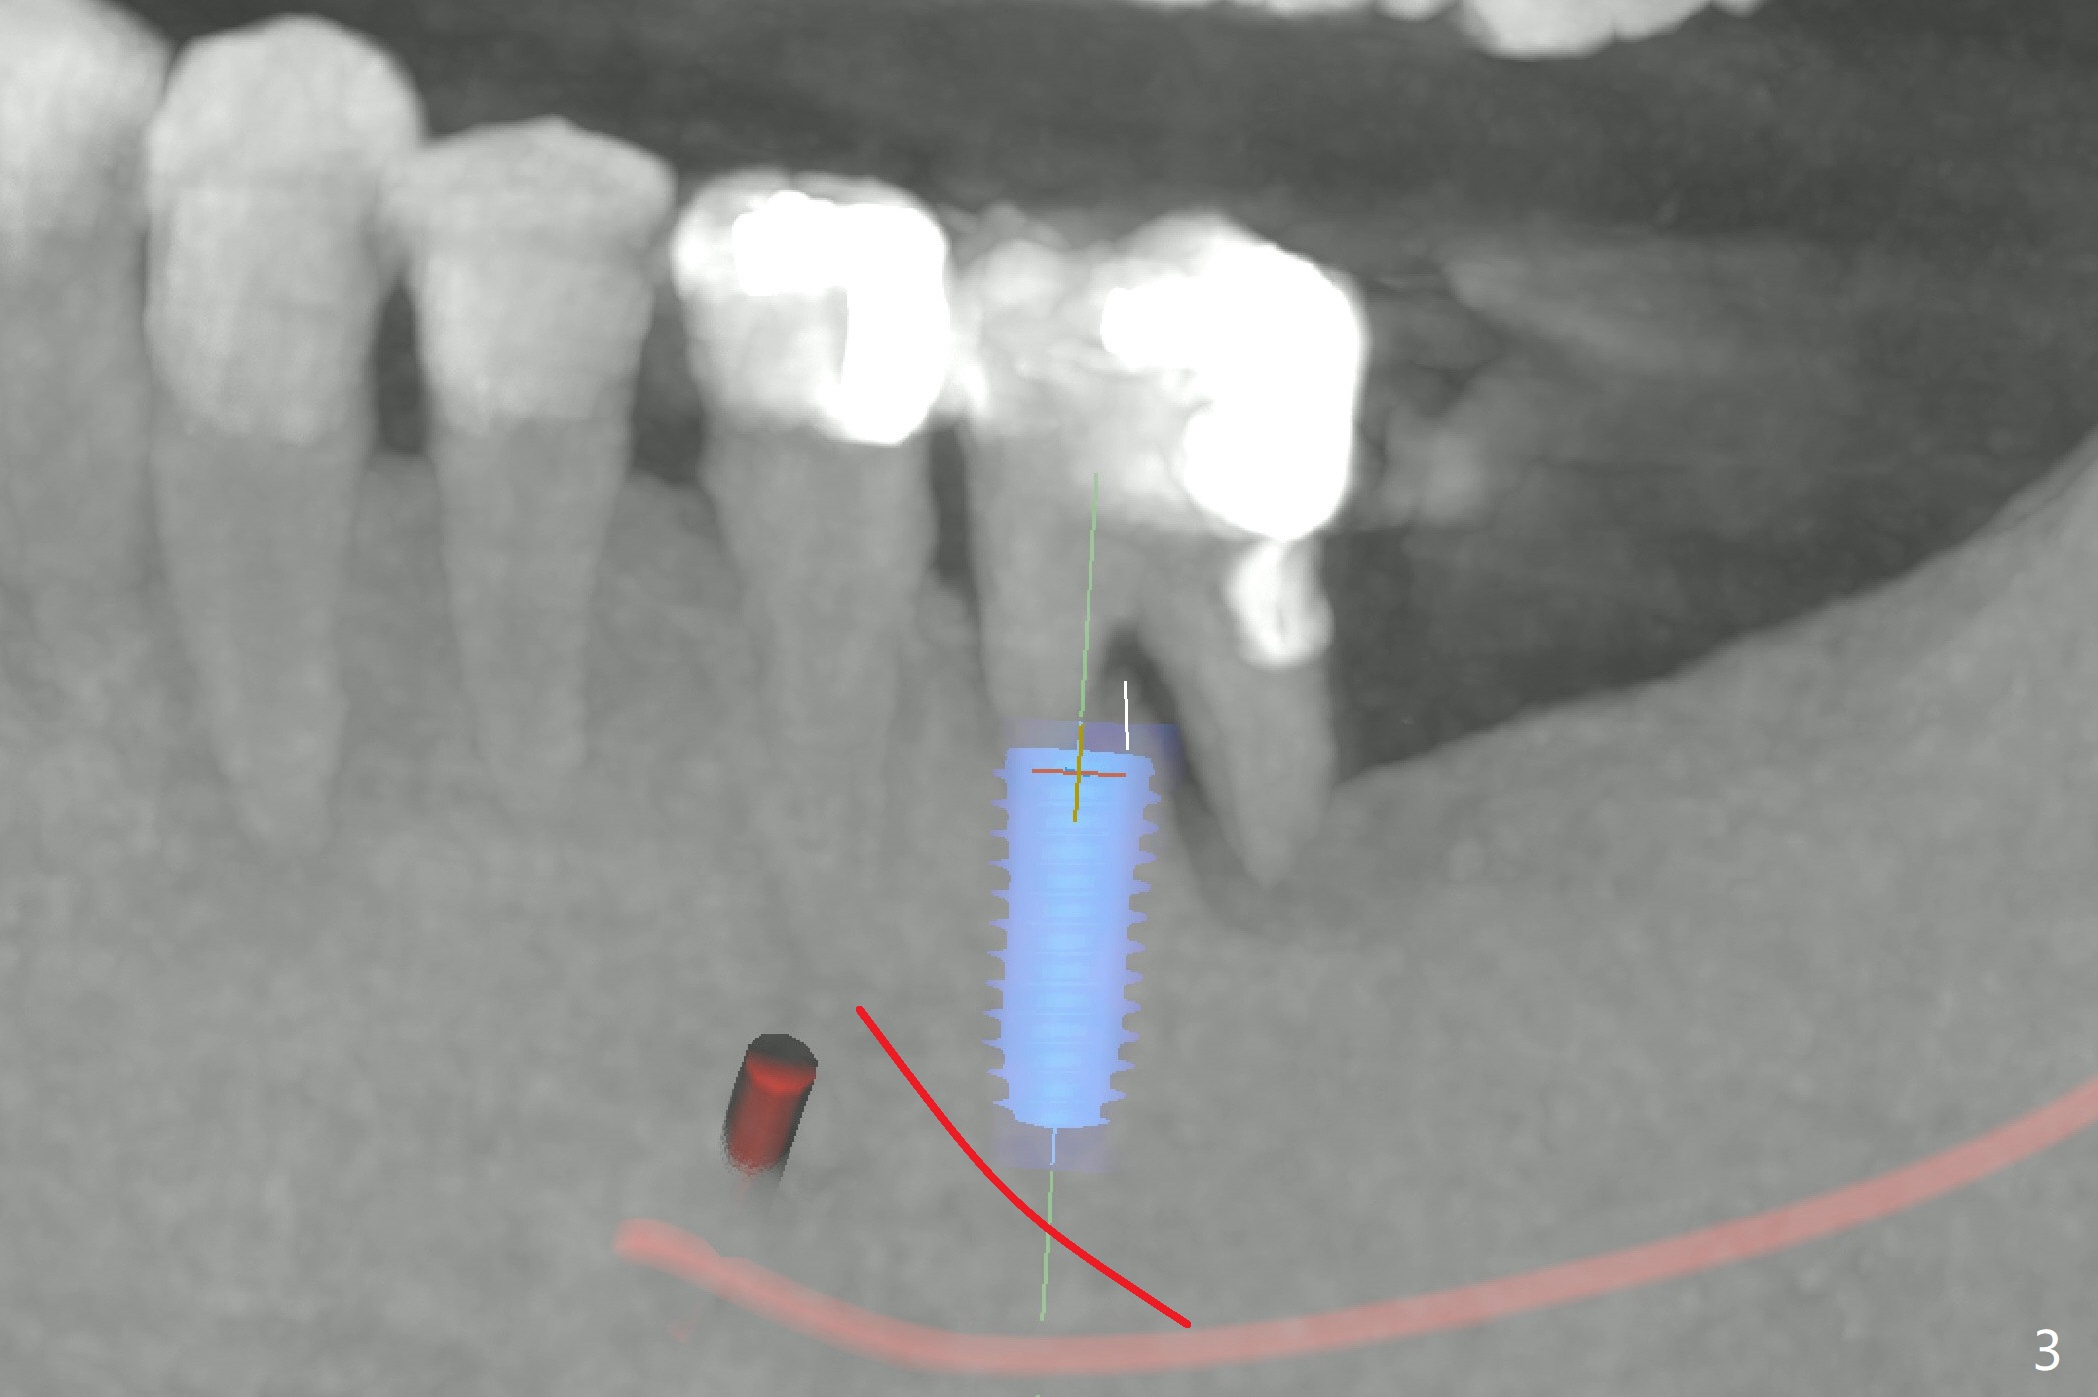

A 49-year-old man agrees to have #19 extracted for implant, 2 years 7 months and 2 years 10 months post cementation at #2 and 31, respectively (Fig.1). Because of severe bone loss in the distal socket of #19, a 4.5x10 mm implant will be placed in the mesial one (Fig.2). To reduce the chance of blockage of blood supply to the tooth #20 (Fig.3 red curved line), the implant will be not placed deep. After osteotomy with guide, a 1.5 mm longer implant will be chosen if there is extra coronal bone as shown in Fig.3 (3D image (white line)).